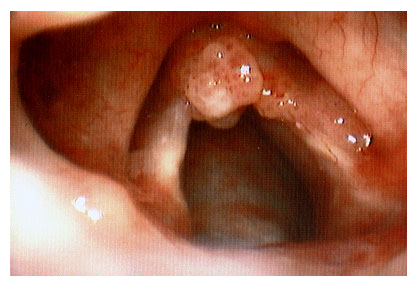

A papilomatose laríngea, uma condição que afeta as cordas vocais, exige atenção especial em diversos aspectos da vida, e a alimentação é um deles. Compreender como certos alimentos podem impactar a laringe e o sistema imunológico é crucial para quem convive com essa questão. O foco principal é fortalecer as defesas do corpo e minimizar os fatores que podem agravar a inflamação local.

O vírus do papiloma humano (HPV) é o principal causador da papilomatose laríngea. Por isso, fortalecer a imunidade é um passo fundamental. Isso significa oferecer ao corpo os nutrientes necessários para que ele possa combater o vírus de forma mais eficaz. Uma resposta imune robusta pode ajudar a controlar a replicação viral e a reduzir a frequência ou gravidade das lesões.

O refluxo laringofaríngeo, muitas vezes chamado de “refluxo silencioso”, é um fator que pode agravar a papilomatose laríngea. Quando o conteúdo ácido do estômago retorna até a região da laringe, ele causa irritação e inflamação. Essa inflamação pode criar um ambiente ainda mais propício para o desenvolvimento ou piora das lesões causadas pelo papiloma.